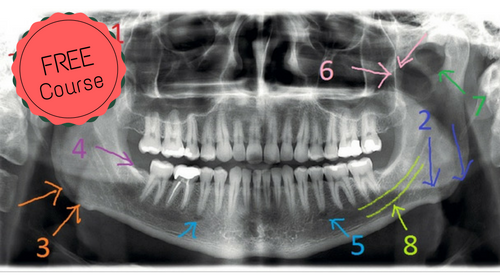

Video + Quiz + Self-study images